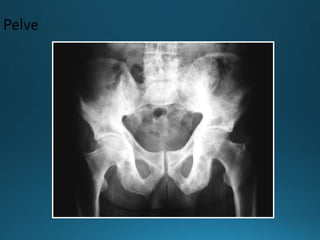

•Pelve:

• Espessamento cortical

• Esclerose das linhas ílio-pectínea e ísquio-púbica

• Asa do ilíaco pode estar envolvida

• Assimétrico (Direita)

• Aumento do ramo púbico e ísquio

Imagem - Rx

Fase mista

Pelve

•Pelve: • Espessamento cortical •Esclerose das linhas ílio-pectínea e ísquio-púbica • Asa do ilíaco pode estar envolvida • Assimétrico (Direita) • Aumento do ramo púbico e ísquio Imagem - Rx Fase mista